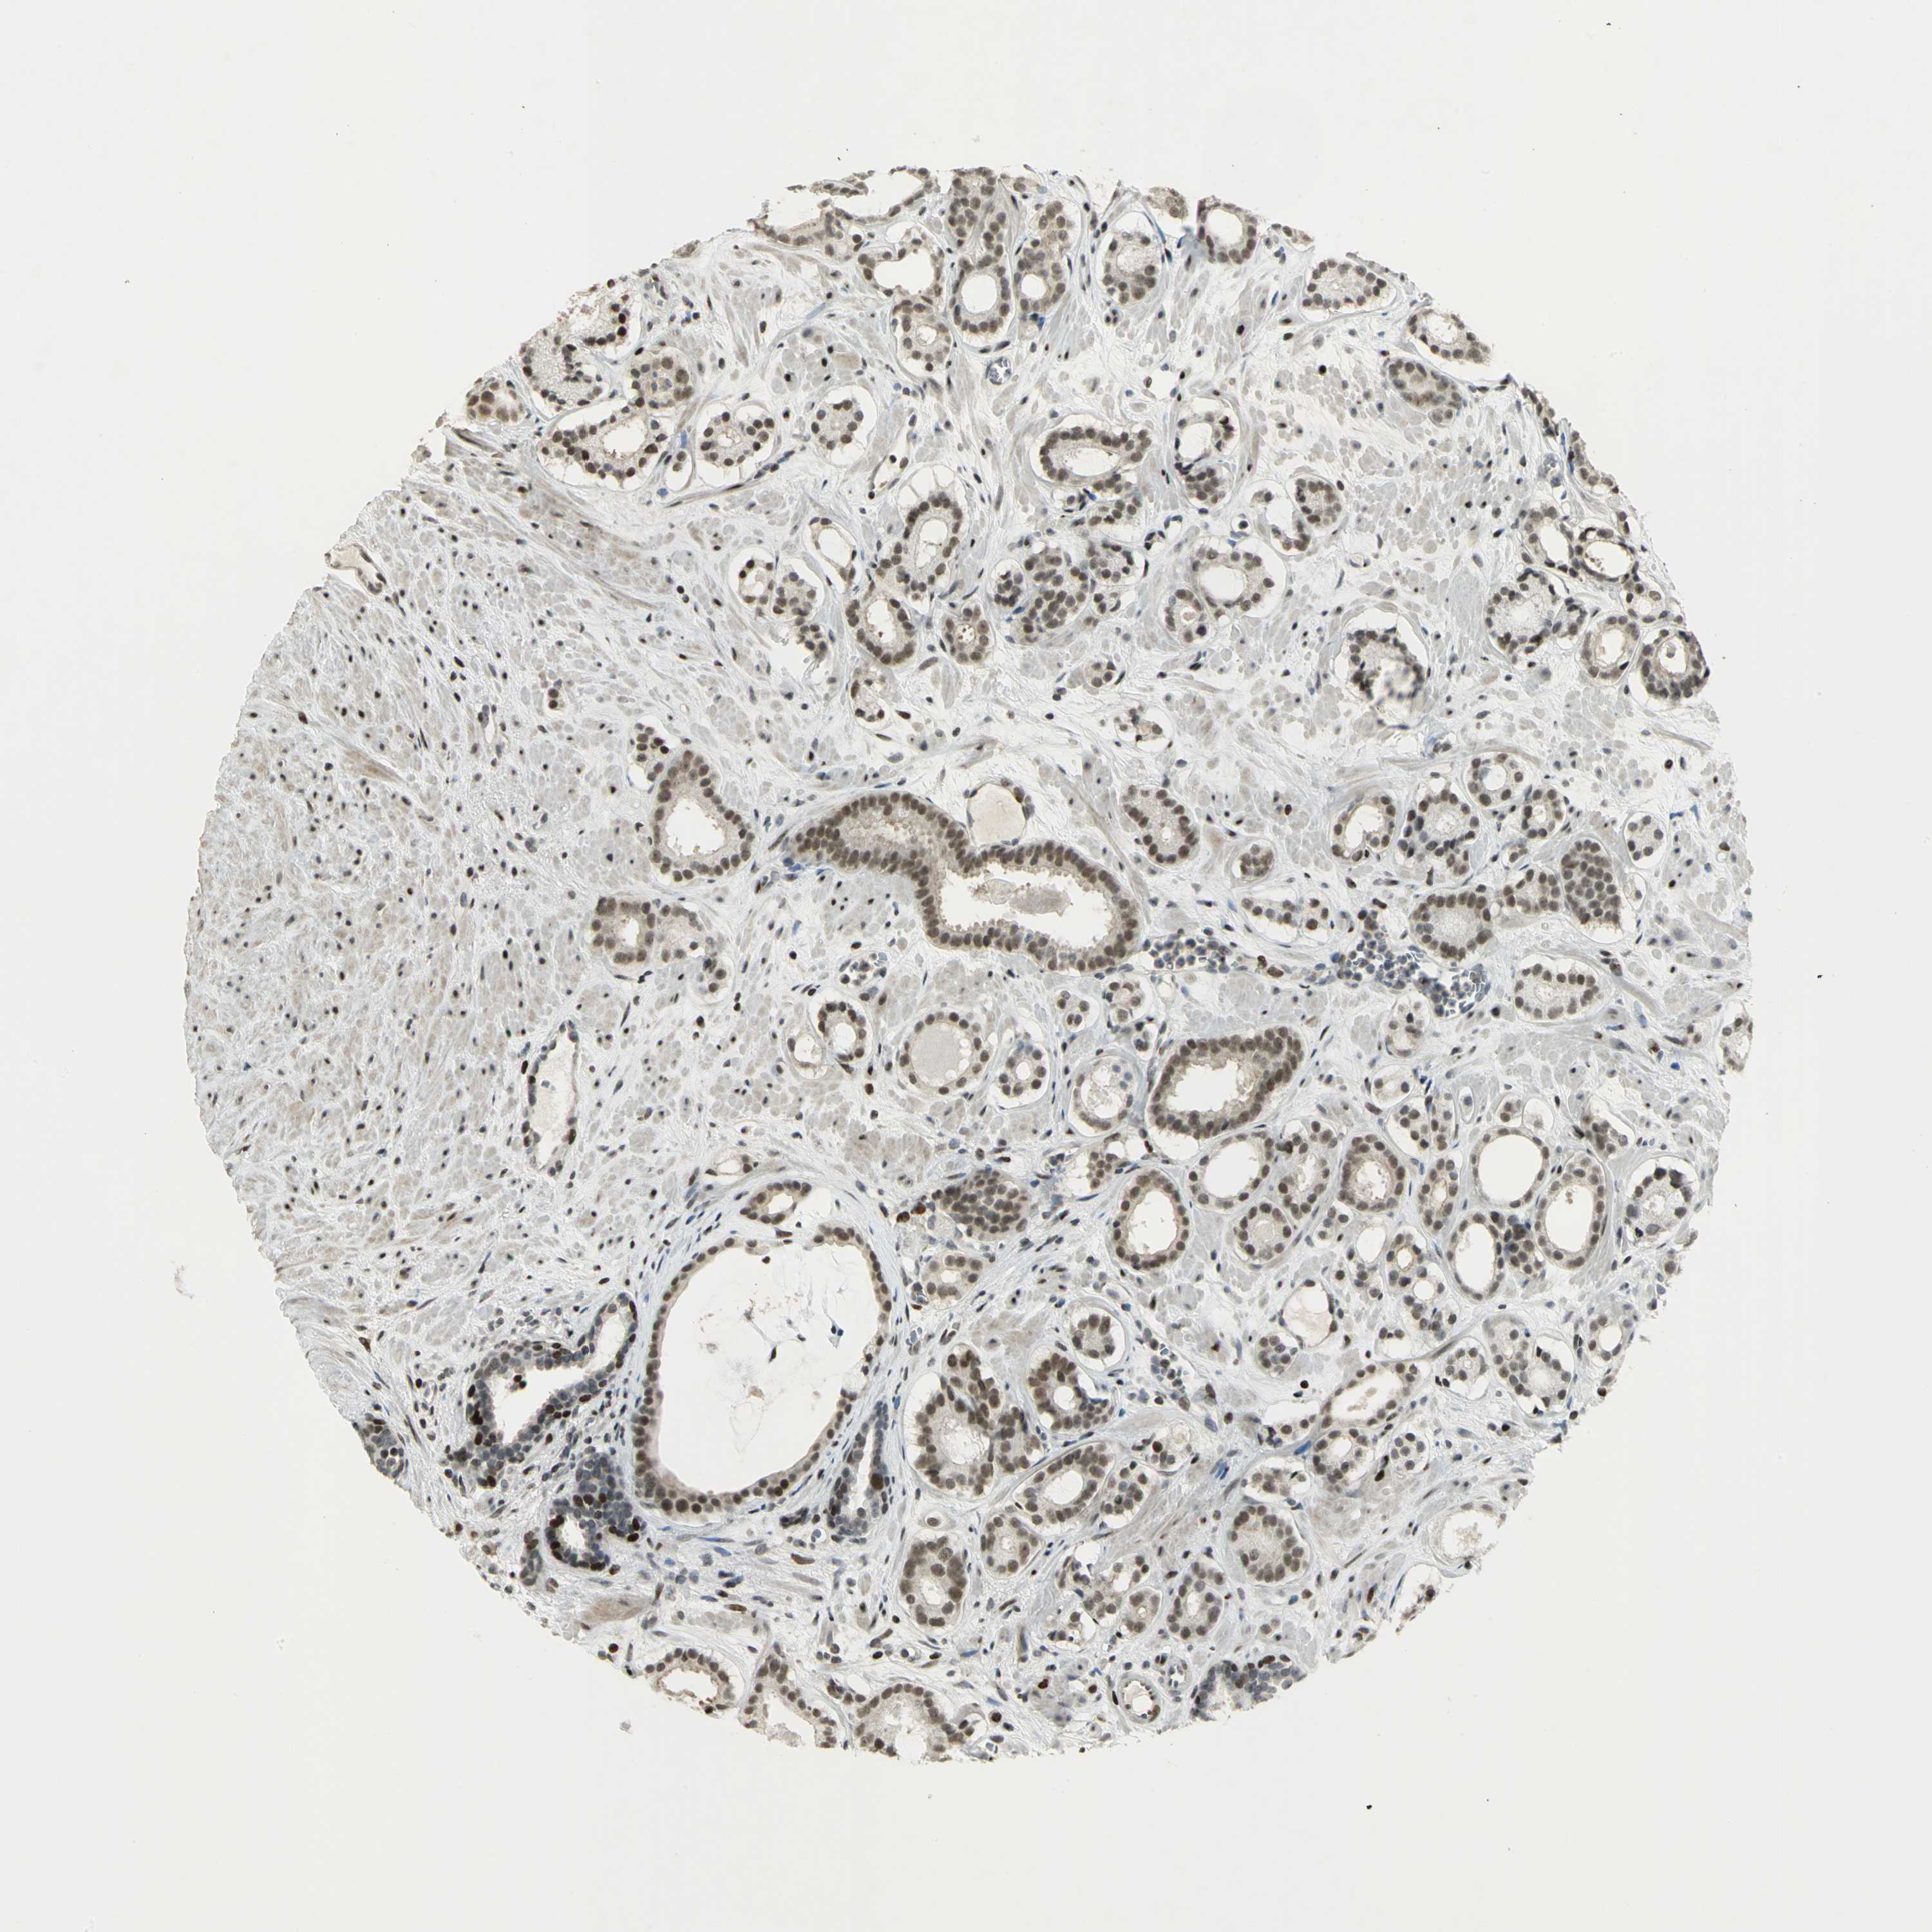

PATHOLOGY

PROSTATE CANCER

Human pathology